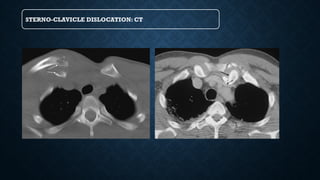

CLAVICLE INJURIES

STERNO-CLAVICLE DISLOCATION: CT